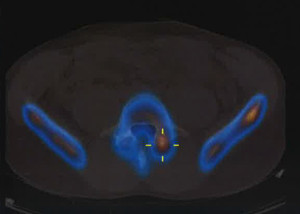

La gran mayoría de los defectos espondilóticos ocurren en el nivel L5 (85 – 95%), siendo L4 el segundo nivel más comúnmente involucrado (5-15%), mientras que las zonas lumbares superiores rara vez se ven afectadas. Este defecto se ve con relativa frecuencia en los estudios radiográficos con vistas posteroanterior y lateral, aunque las vistas dinámicas y oblicuas parecen determinar la estabilidad vertebral y conducir al diagnóstico.

Desafortunadamente, se realizan diagnósticos erróneos de espondilólisis. Un factor de complicación en las primeras etapas de la enfermedad que conduce a un diagnóstico erróneo es el hecho de que las radiografías simples, incluso las oblicuas, pueden no ser útiles en la etapa de fractura por sobrecarga. Otras técnicas de imagen, como la gammagrafía ósea, posiblemente, la resonancia magnética o Tomografía computarizada de emisión monofotónica (SPECT) deben ser utilizadas al inicio del proceso de diagnóstico. En el ámbito de la atención primaria, el diagnóstico precoz de elemento de participación posterior relacionado con el dolor lumbar, ya sea en la etapa de la fractura por sobrecarga del pars o por espondilolisis temprana, puede prevenir la progresión de la enfermedad y evitar la necesidad de una intervención quirúrgica.